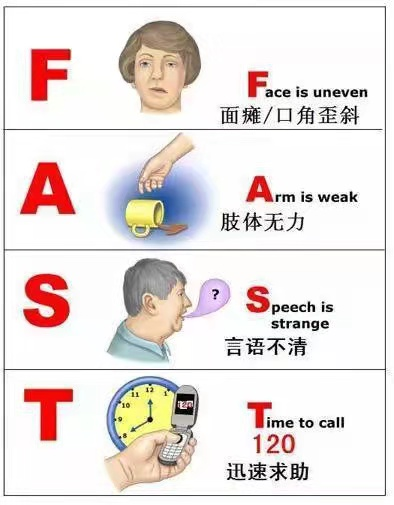

时间就是大脑,时间就是生命。2003年,国际上推出一套公众自我识别3个卒中症状的方法:一是脸不对称、二是胳膊抬不起来、三是说话不清楚。

“F”——Face是指面部,面部不对称,口角歪斜;

“A”——Arms是指手臂,手臂突然无力感或麻木感,通常出现在身体一侧;

“S”——Speech是指语言,说话含混、不能理解别人的语言;

“T”——Time是指时间,上述症状提示可能出现卒中,请勿等待症状自行消失,立即拨打120获得医疗救助。